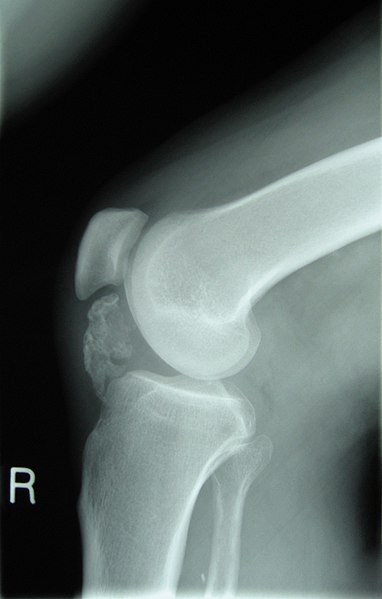

Radiografías óseas

Las radiografías óseas pueden ayudar a identificar todo tipo de problemas esqueléticos, como:

– Osteoporosis

– Fracturas

– Artritis

– Infecciones óseas

– Cáncer de hueso

– Alineación de la columna